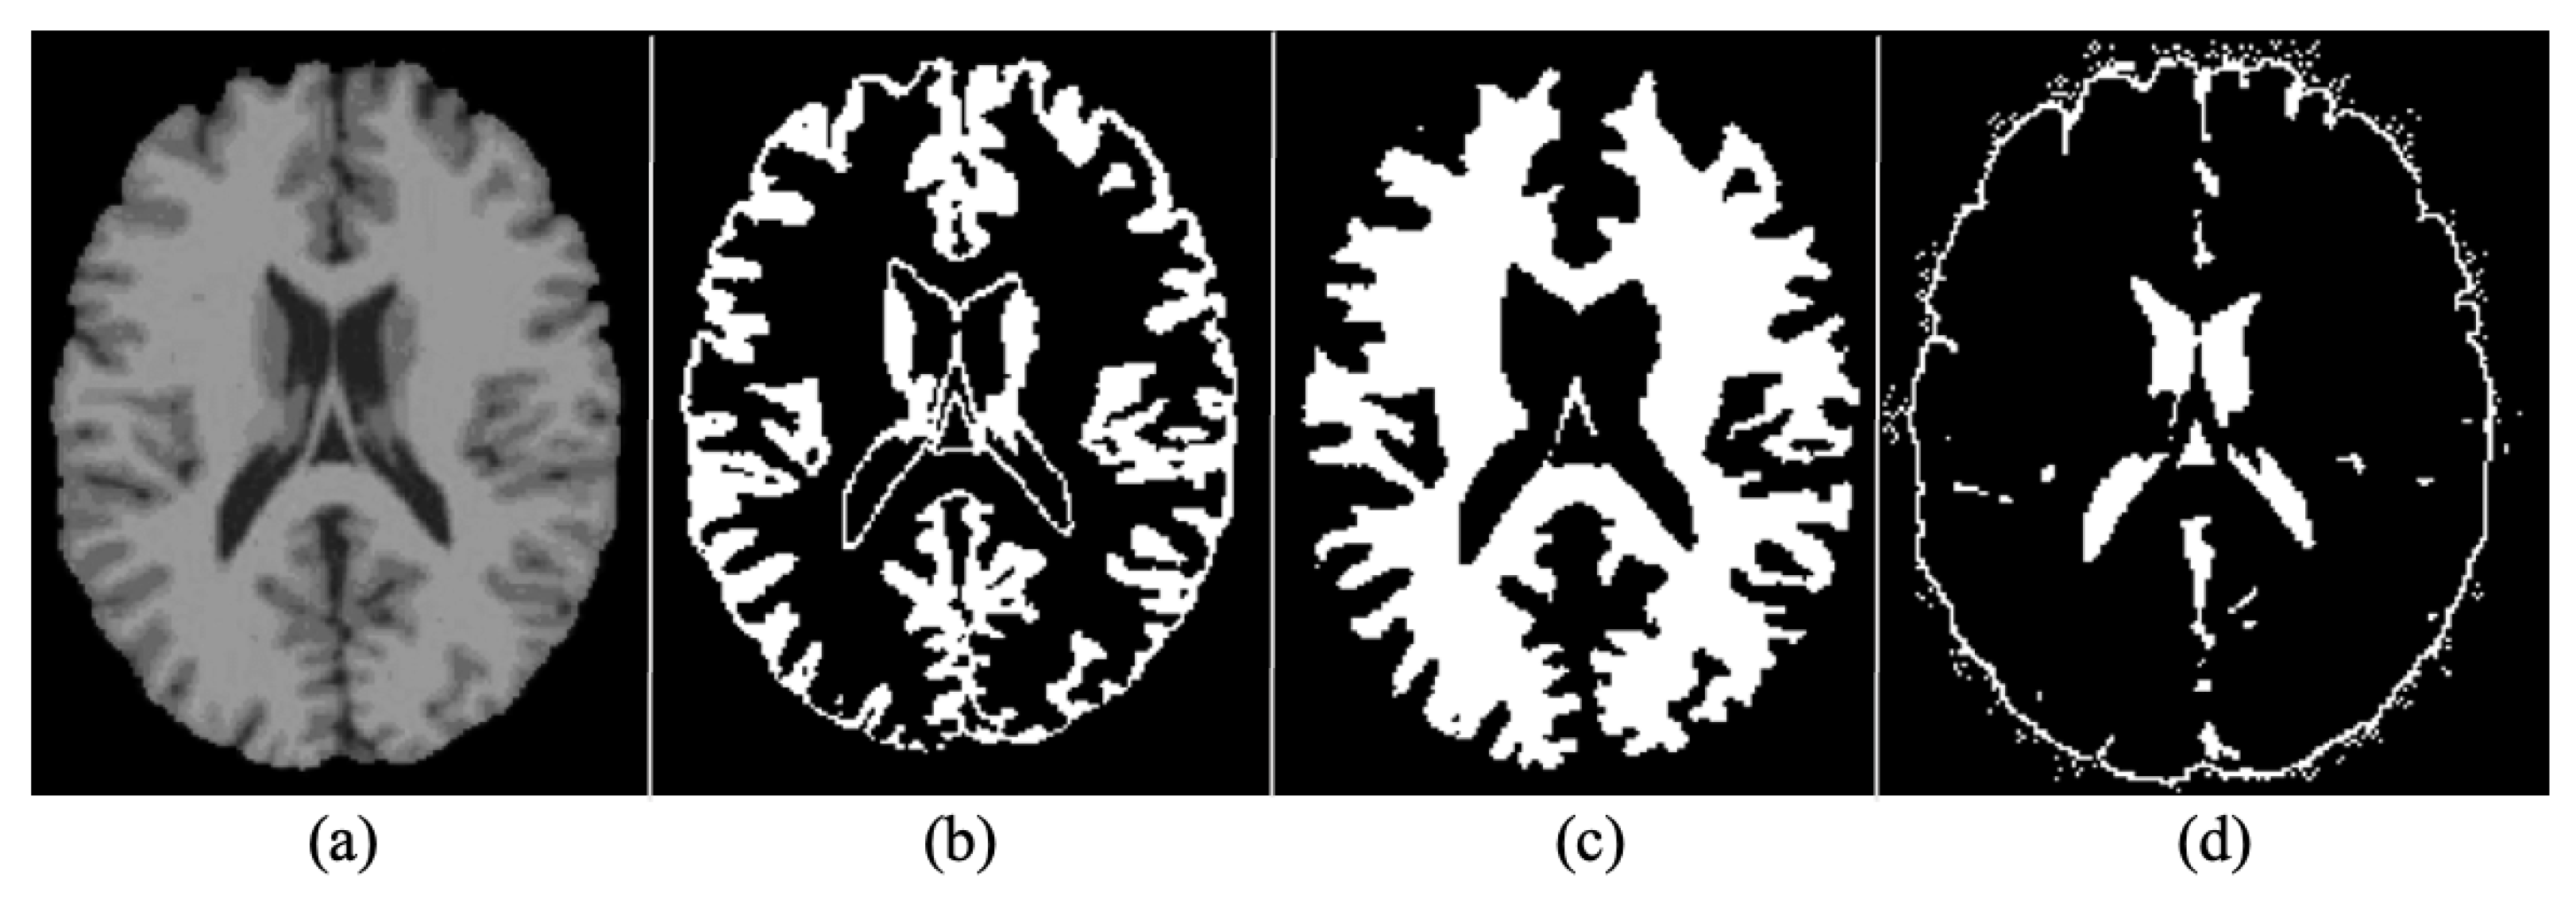

4.2.2. Segmentation

4.2.3. Normalization

4.2.4. Rescaling